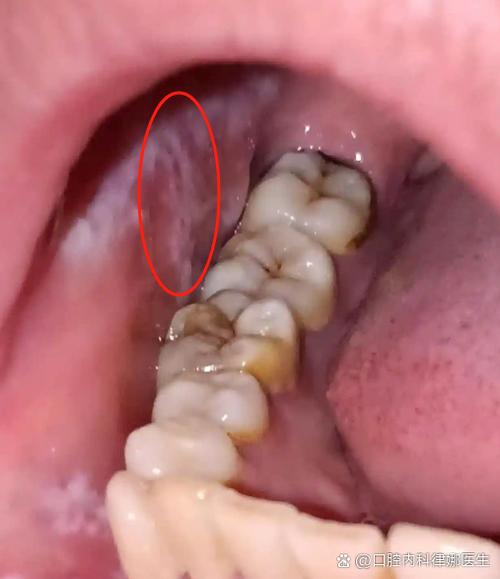

口腔白斑

这是一种癌前病变,虽然大部分白斑终身不会癌变,但有癌变的风险,它指的是口腔黏膜上出现的、不能用任何物理方法(如擦除)去除的白色或灰白色的斑块。

- 特点:

- 表面粗糙、质地较硬,有时有裂纹或溃疡。

- 边界清晰,形状不规则。

- 关键点:虽然初期可能无痛无痒,但需要定期复查,因为存在一定的癌变率。特别是长期吸烟、饮酒、嚼槟榔者,是高危人群。

扁平苔藓

一种原因不明的慢性炎症性皮肤病,也可累及口腔黏膜,口腔扁平苔藓的皮损有多种形态,其中一种就是网状或斑片状的白色条纹(Wickham纹)。

- 通常伴有轻微的灼痛或粗糙感,但有时也可以是无症状的。

- 白色条纹常呈“树枝状”或“网状”,周围黏膜可能正常或发红。

- 有一定的癌变风险,需要定期随访。